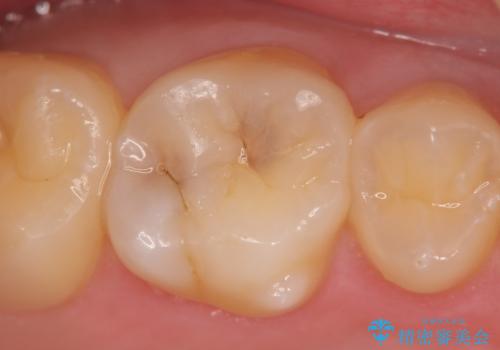

検診による初期虫歯の早期発見・早期治療

- 検診を希望され来院されました。

症状は特にありませんでしたが、検診で全体をチェックすることで虫歯を小さなうちに早期発見し治療することができました。